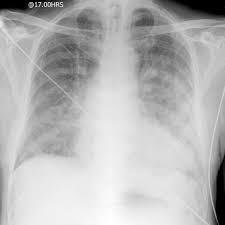

Radiographie thoracique: en retard sur la clinique

. cardiomégalie (augmentation du rapport cardia-thoracique)

. permet de juger du degré d’élévation des pressions gauches

. redistribution vasculaire au sommet/ oedème interstitielle (ligne de Kerley)/ oedème alvéolaire/ épanchement pleural (plus souvent à droite)

Radiographie thoracique: signes en faveur d’un OAP

. Épaississement de la trame vasculaire

. Redistribution vers les sommets avec lignes de Kerley (syndrome interstitiel)

. Œdème alvéolo-interstitiel

. Opacité floconneuses, mal limitées, bilatérales et symétriques, prédominant aux hiles (en ailes de papillon)

. Adénopathies hilaires et médiastinales

. Épanchement pleural

. Cardiomégalie